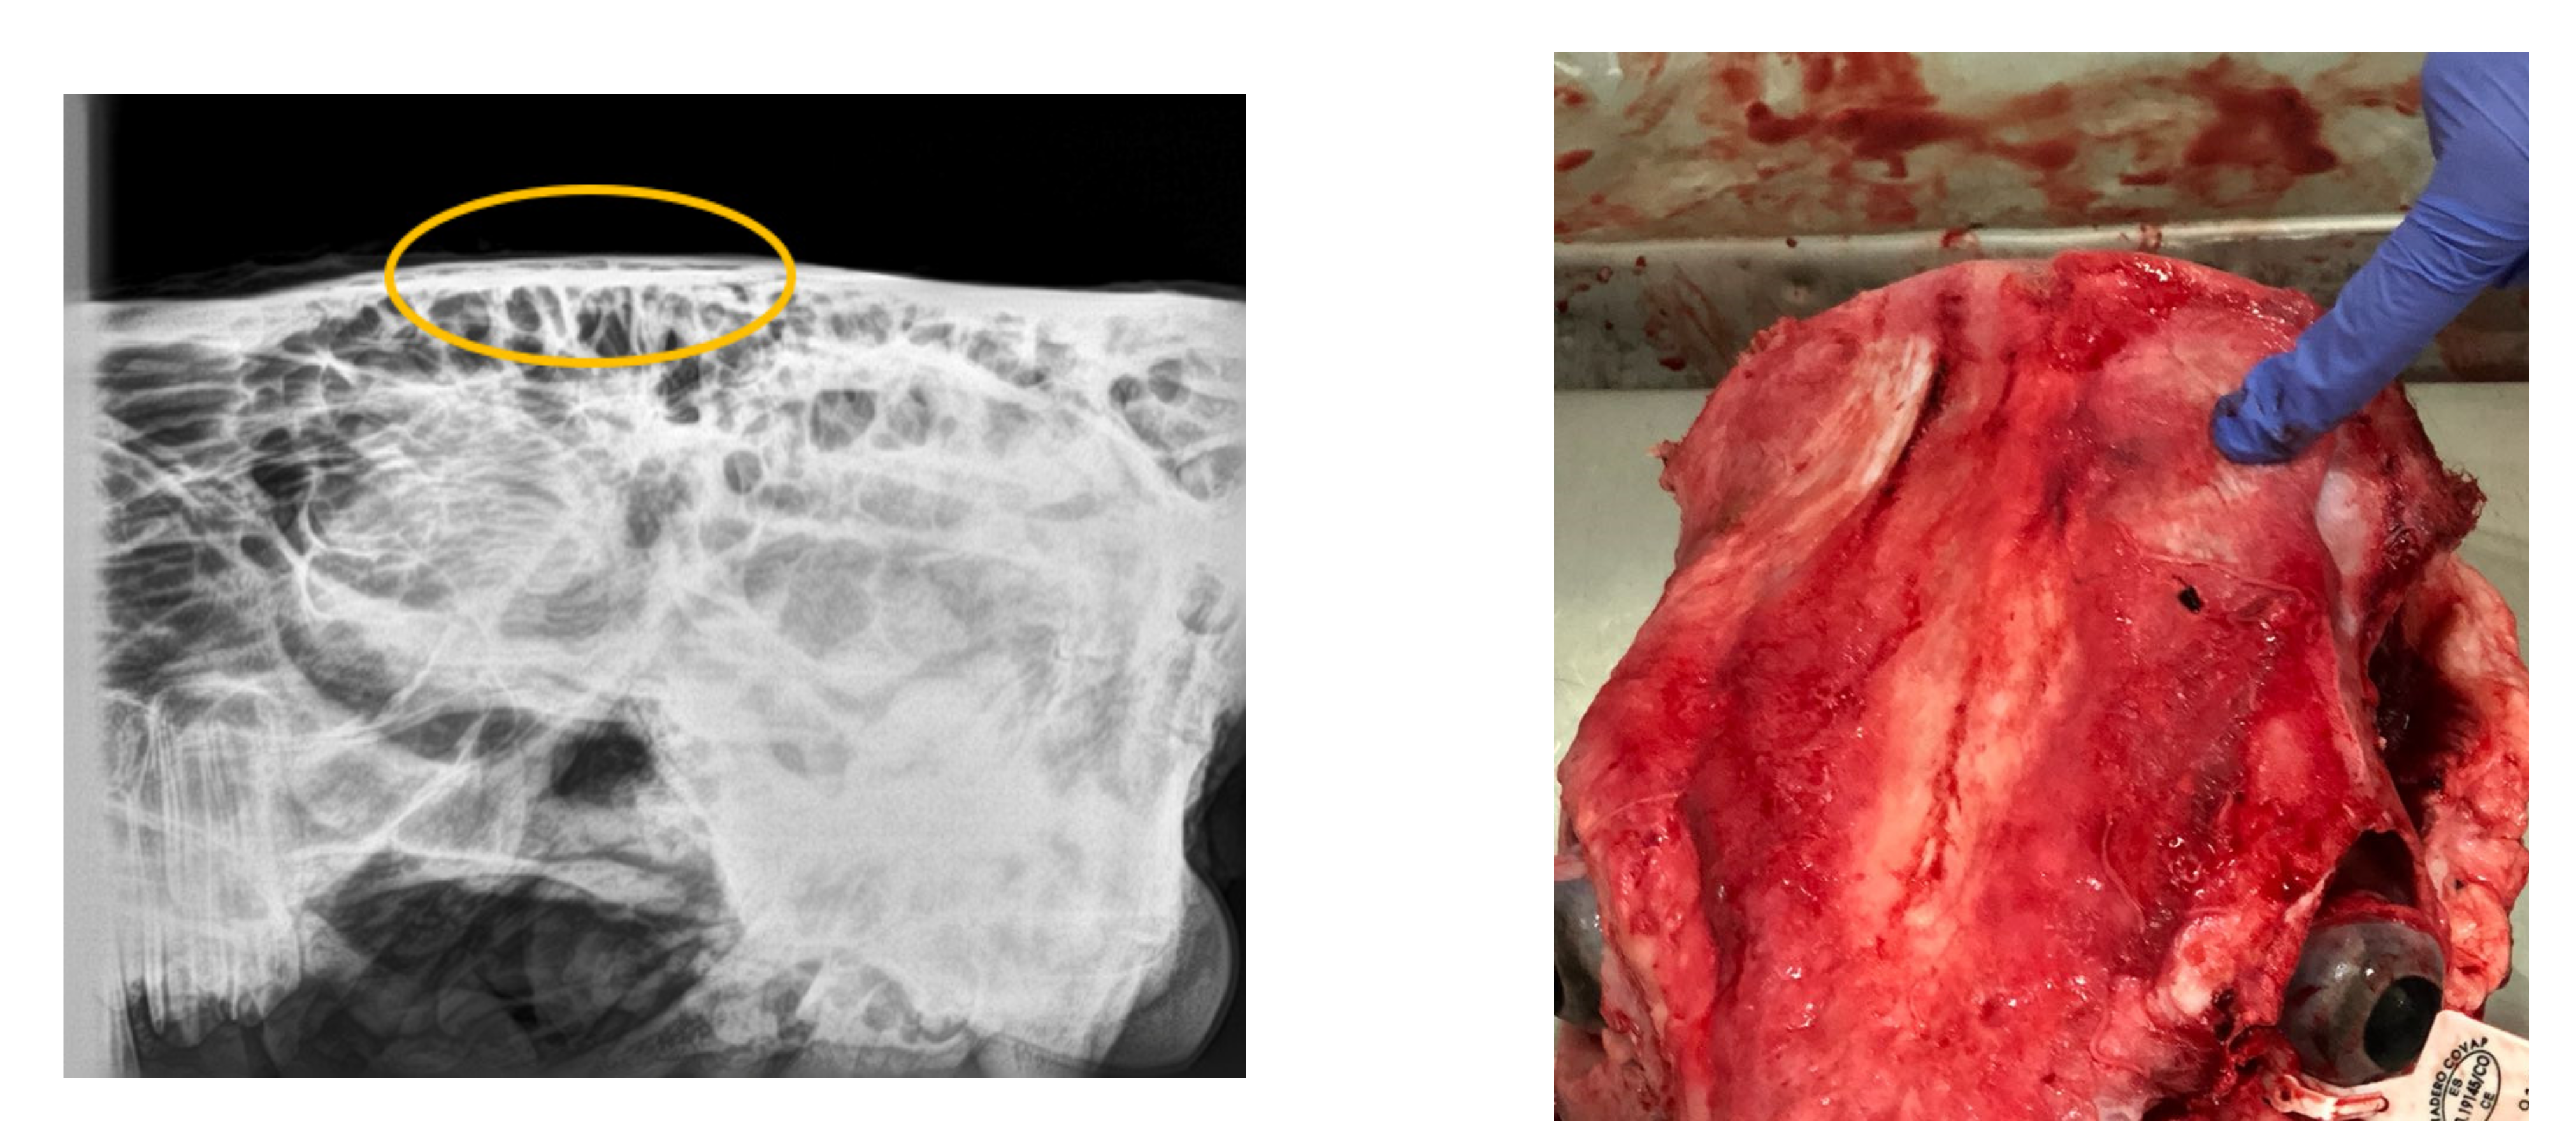

Regarding the radiographical study, it was observed that the skulls presented rating 1 “no visible damage” (70%) or 2 “indentation no cracking” (20%), and rating 3 “indentation with cracking but no displacement” (10%) following the Malaysia Standard (Figure 3, Figure 4, Figure 5). Consequently, 90% of the HSS animals (ratings 1 and 2) would be accepted for halal commercialization. However, no radiographical differences existed between ratings 1 and 2 (Figure 3 and Figure 4); only macroscopic differences in soft tissues were noted.

Figure 4.

Digital radiography rating 2 (following Malaysia Standard 1500:2009), and related photograph.